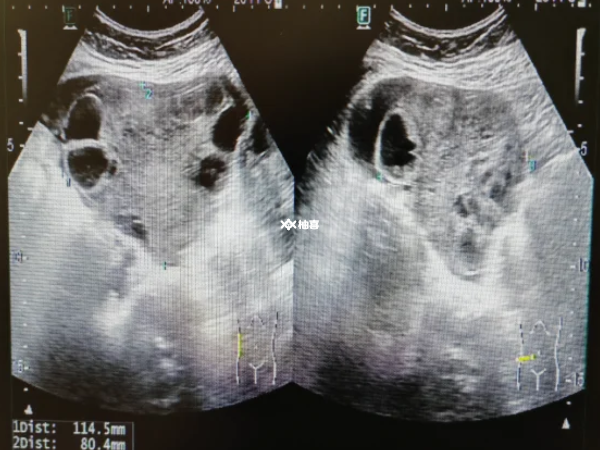

卵子存活时间和卵巢功能密切相关,卵巢功能直接影响着卵子的质量、排出以及生存环境。卵巢功能良好时,能够为卵子的发育提供充足的营养和适宜的环境,促使卵子成熟度高、质量好。这样的卵子细胞结构完整,细胞质饱满,含有足够的能量和营养物质,具备较强的生命力,在排出后能够存活相对较长的时间。